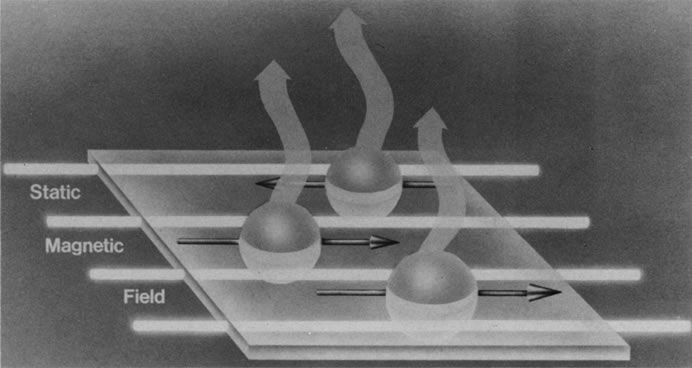

The nucleus of an atom contains protons (positive charge) and neutrons (no charge), and each of these elementary particles spins on its own axis. Because of a relationship between electricity and magnetism, the electric charge and spin of these particles produce a small local nuclear magnetic field. In nuclei with an even mass number (an even number of protons and neutrons), the spinning particles are paired and their magnetic properties cancel. However, in nuclei with an odd mass number, such as hydrogen, sodium, and phosphorus, these spinning particles produce a net magnetic moment. Such nuclei behave as magnetic dipoles and respond to external magnetic fields (Fig. 1).1,5,11–14

Hydrogen, which contains a single proton, has the largest magnetic moment of all stable atomic nuclei and is highly prevalent throughout biologic tissues. For these reasons, hydrogen forms the basis for MRI and exemplifies its principles. In nature, the magnetic moments of the hydrogen nuclei in biologic tissues are randomly oriented and therefore exhibit no net magnetic effect (Fig. 2). When these nuclei are placed in a strong static magnetic field, such as that produced in an MRI unit, they line up parallel or antiparallel to the field. Slightly more align parallel to the main magnetic field, because this is a lower energy state, and produce a net magnetic vector in this direction (Fig. 3).1,5,8